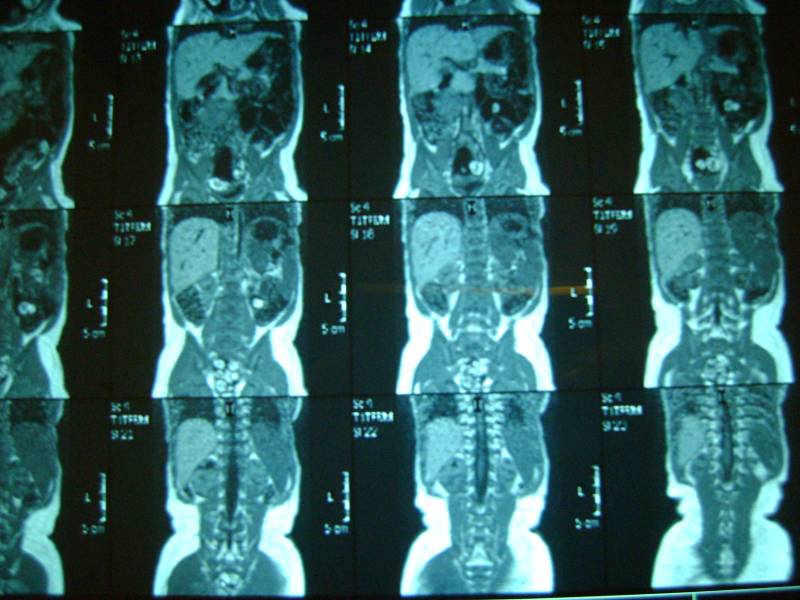

еще